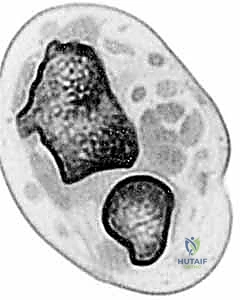

* CT Scans: These are invaluable, especially for assessing bony morphology and subtle subluxation.

* Crucially, CT must be performed on both wrists, with images obtained in identical forearm rotation (typically neutral) for direct comparison. This allows us to quantify translation and identify incongruity.

* Consider adding stress views during imaging to unmask subtle instability.